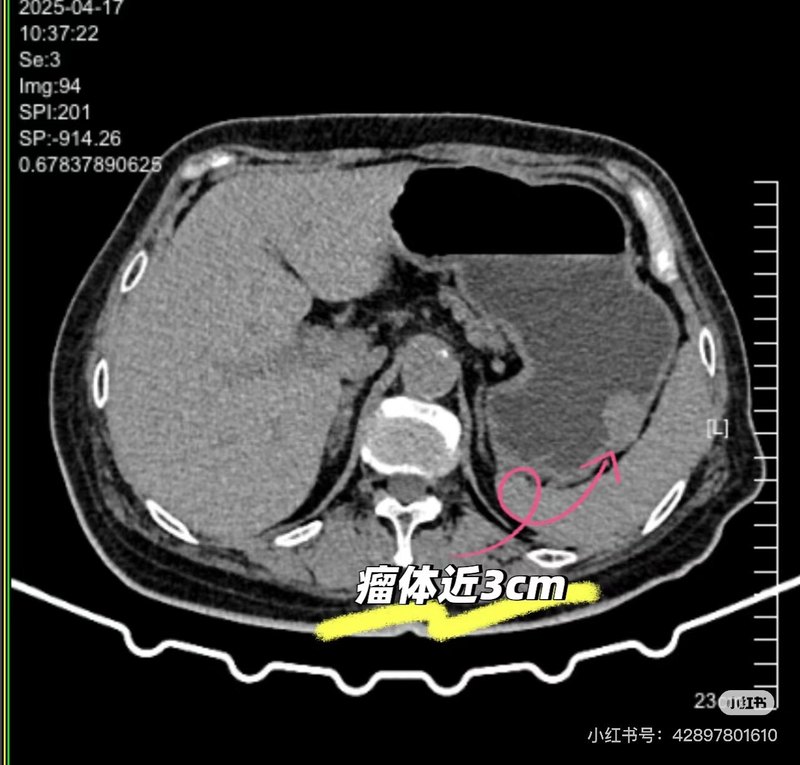

周末在家鄉(xiāng)縣醫(yī)院與當(dāng)?shù)蒯t(yī)生協(xié)作完成一例考慮胃間質(zhì)瘤內(nèi)鏡下EFTR術(shù)(全層切除術(shù))?;颊呶哥R查出2-3cm黏膜下隆起,質(zhì)地較韌,胃內(nèi)此種病變絕大多數(shù)考慮間質(zhì)瘤。因當(dāng)?shù)乜h醫(yī)院超聲內(nèi)鏡購(gòu)買中,還未到位?;颊哂值膺^(guò)敏,因此術(shù)前只能行上腹部CT平掃,充分喝水撐開(kāi)胃腔后,瘤子輪廓較清晰。溝通交流后,家屬充分信任,考慮內(nèi)鏡下微創(chuàng)切除。手術(shù)非常順利,瘤子完整切除,避免了外科腹腔鏡/開(kāi)腹手術(shù)。術(shù)后病灶性質(zhì)明確及是否需要進(jìn)一步靶向藥口服等有待進(jìn)一步病理評(píng)估。結(jié)合病例診療談?wù)剮c(diǎn)感悟:1.充分的術(shù)前評(píng)估很重要,有時(shí)候不可能裝備精良,那也得用好手頭已有的武器,此例患者沒(méi)有做超聲內(nèi)鏡條件,術(shù)前CT評(píng)估做得很漂亮,患者自身準(zhǔn)備的好,水喝的很足,病灶顯示也很清楚。2.多與相關(guān)科室進(jìn)行討論,術(shù)前與兄弟科室普外科交流討論,明確手術(shù)適應(yīng)癥、禁忌癥。做好多種方案,有備無(wú)患。3.與患方多溝通交流,解答對(duì)方困惑,建立良好醫(yī)患信任?;挤椒菍I(yè)人士,難免有困惑及焦慮。淺顯易懂將治療相關(guān)原理與可能發(fā)生情況及應(yīng)對(duì)策略告知他們后,不但有助于他們解除困惑及焦慮,也有助于建立和諧醫(yī)患關(guān)系。4.引用我科熊光蘇主任科普相關(guān)文@消化內(nèi)鏡熊光蘇醫(yī)生。消化道疾病提倡早診治療,以胃腸道間質(zhì)瘤為例。絕大部分小瘤子(小于1cm)可以選擇定期內(nèi)鏡隨訪,但是越大的瘤子,惡變風(fēng)險(xiǎn)越大(量變引起質(zhì)變),較大的瘤子還是建議切除,具體是內(nèi)鏡還是外科還需具體評(píng)估。5.對(duì)于一些交界性大小病變(例如1cm左右的),切還是不切的糾結(jié)問(wèn)題。我個(gè)人建議是:綜合年齡及患者個(gè)人心態(tài),如果能夠接受定期復(fù)查不想切,可以選擇隨訪。如果心態(tài)上就有定時(shí)炸彈????思想,那還是早點(diǎn)前往權(quán)威醫(yī)院尋求經(jīng)驗(yàn)豐富醫(yī)生行切除治療,一勞永逸。